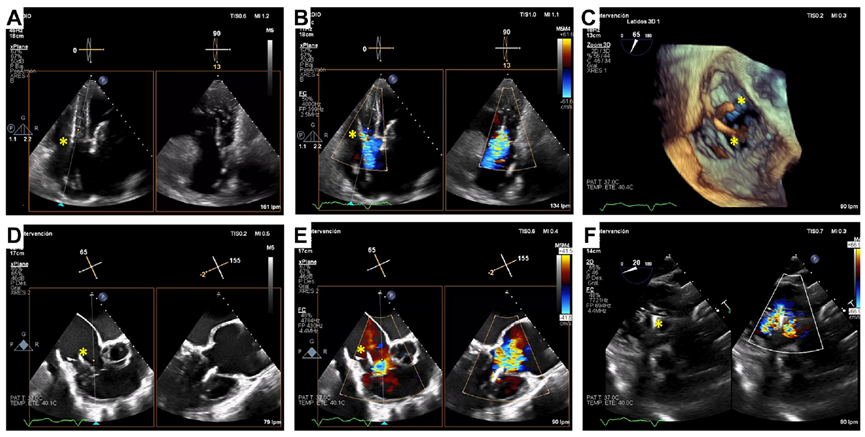

基線經(jīng)胸和經(jīng)食道超聲

術后經(jīng)食道超聲,僅微量瓣周漏

起搏器/ICD導線引起的TR是三尖瓣反流的主要機制,這也是三尖瓣介入治療面臨的極大挑戰(zhàn)。既往臨床實踐已證實LuX-Valve系列產(chǎn)品在高危三尖瓣反流患者中的安全性和有效性,并且術后并發(fā)癥發(fā)生率低。LuX-Valve系列產(chǎn)品瓣膜應用室間隔“錨定區(qū)域”作為特殊的錨定機制,保證了瓣膜的穩(wěn)定性。同時,多種尺寸的、較大的自適應防漏環(huán)可有效避免瓣周漏的發(fā)生,所以對于術前有起搏器/ICD植入史的患者,LuX-Valve系列產(chǎn)品可以最大程度減少由導線引起的三尖瓣殘余反流。本文報道的病例有兩根導線,其中一根材質(zhì)較厚,位置在瓣膜的中心,手術的結(jié)果依然很完美。尤其是,LuX-Valve系列產(chǎn)品經(jīng)導管三尖瓣置換系統(tǒng)的調(diào)整和釋放是在緩慢而完全受控的情況下進行的,術者可精確定位和控制導線的位置。隨訪期間,LuX-Valve Plus瓣膜沒有出現(xiàn)衰敗或血栓的現(xiàn)象,患者生活質(zhì)量也大為改善。